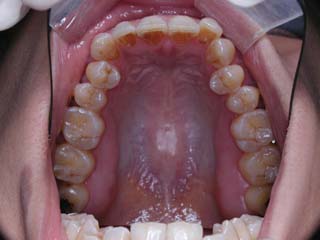

この症例では、上顎にリンガルブラケット矯正装置(Kurz)が用いられています。

使用した主な装置名:TPB、上顎リンガルブラケット矯正装置、下顎マルチブラケット装置、オーソアンカー SMAPシステム

本症例について検査診断の結果、開咬、叢生、下顎前突傾向を認めました。患者希望を考慮し、治療メカニクスとして、非抜歯配列、上顎のみリンガルブラケット矯正装置、下顎唇側マルチブラケット矯正装置、および、目的外使用のオーソアンカー SMAPシステムを用いることにいたしました。

非抜歯の計画でしたが、下顎臼歯はかなり遠心移動をする予定になっていますので、親不知はあらかじめ抜歯をお願いしました。